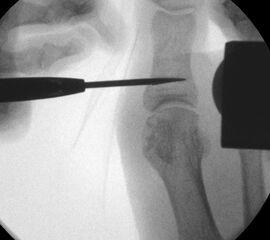

• Röntgenaufnahme des Fußes (unter Belastung) in dorsoplantarem und seitlichen Strahlengang (Abb. 3) und präoperative Fotodokumentation.

• Bildverstärker.

Operationstechnik (Text und Fotos)